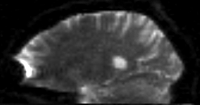

RegLib C32 unregistered.png unregistered pair of T1 and DTI (click to enlarge)